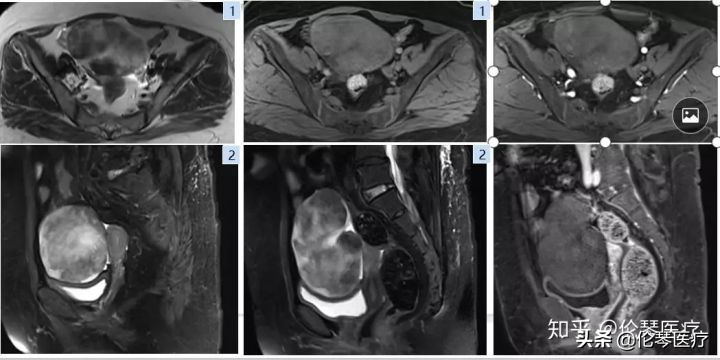

磁共振的另一优势在于多方位成像,成像范围大(大FOV),这也是基于卵巢肿瘤本身具有的特点。因为卵巢肿瘤通常会长很大,占据整个腹部,超声对于这么大的肿瘤,很难了解到细节。而磁共振多方位成像就可以全面了解肿瘤的上下左右关系,以及肿瘤和血管之间的关系。

如图所示病例,初步诊断是常见的卵巢上皮癌,后来通过磁共振的多方位成像,发现肿瘤在腹腔里有几个组成部分,且发现上腹部的胃也有问题。最后,我们术前诊断是胃癌到卵巢的转移,称为库肯勃氏瘤。